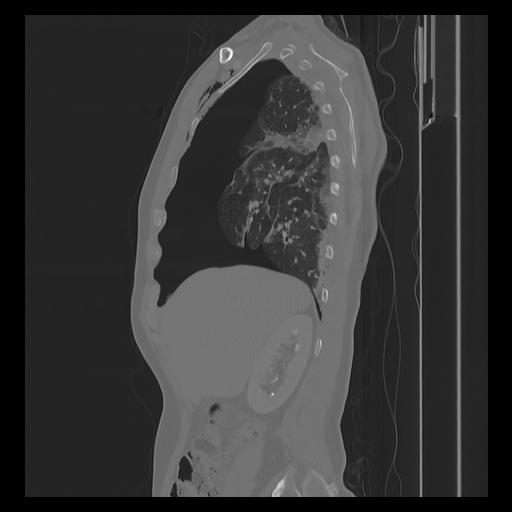

33 PULMON,CE,Sagittal,3.000,PULMON,Sagittal,